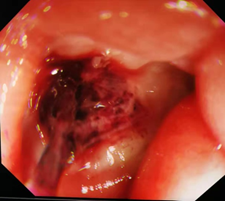

事情要从2019年08月06日中午说起,医生们刚吃过午饭,狂风大作,雷雨交加,医疗二线朱质斌医师接到急诊科电话,说有一个“呕血、失血性休克”的病人需转入病房,肝病四科医护人员立即待命,做好各项准备……患者陈**,34岁男性,当天9:30在公司上班时感上腹部不适,呕吐鲜红色血液约600ml,伴头晕,大汗淋漓,四肢厥冷,突发晕厥,立即由120送入深圳市第三人民医院急诊科, 2017年也曾因“呕血”在外院治疗,当时诊断考虑“十二指肠球部溃疡出血”,患者在转运过程中及急诊科内分别呕吐鲜血400ml、300ml,测血压84/58mmHg,转入病房后给予双倍止血、抑酸护胃药物治疗,开通多条静脉通道加强补液,血压92/60mmHg,再次呕鲜血200ml,查血红蛋白100g/L,肝病四科陈军主任决定立即请内镜中心、介入科会诊,经商议后,转入胃镜室行急诊胃镜下止血治疗,张卓主任亲自挂帅,带领团队积极救治病人,镜下可见十二指肠球部一深大溃疡,由于溃疡表面质地异常坚硬,止血夹无法夹闭溃疡,予以注射组织胶共3个位点,反复观察未见活动性出血,撤镜,

患者于21:30送入手术室,拟行全麻下剖腹探查术,结果一进手术室就开启了抢救模式,血压最低降至60/30mmHg,心率从100次/分降至60次/分以下,血红蛋白机器测不到,直至输注O型8U红细胞,才测得血红蛋白65g/L,事实上当晚一肝移植手术患者也需要O型血,输血科杨燕主任积极备血,保证稀缺的O型血血液供应,经补液、扩容、升压处理后,生命体征趋于平稳,22:45开始手术,术中探及十二指肠球部溃疡如盾牌般坚硬,手术针在它面前都“折了腰”,且与周围组织粘连紧密,不易分离,电刀辅助打开胃前壁下1/3,十二指肠球部惊现“红色小喷泉”,予以缝扎止血,并解剖结扎离断胃右动脉及胃十二指肠动脉血管,行十二指肠旷置、胃大部切除术,术中从肠道内吸出约1500ml肠型血凝块。